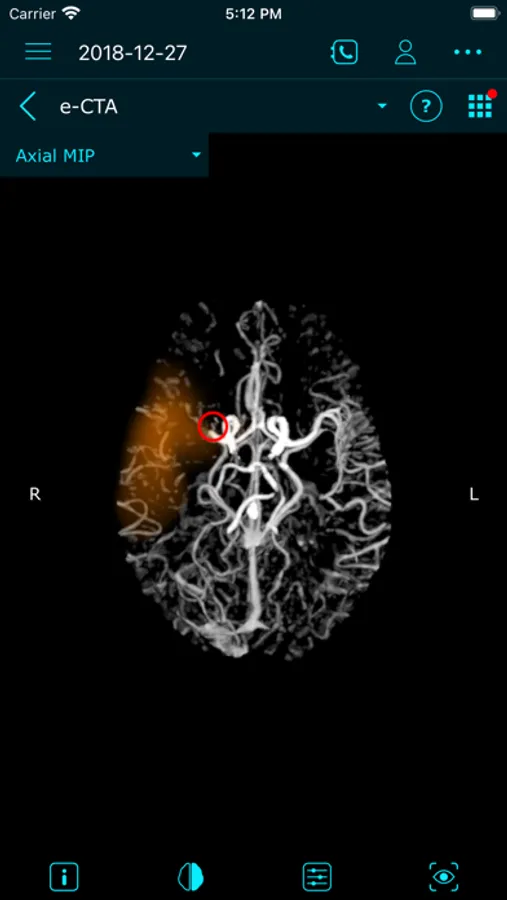

e-Stroke consists of three modules (e-ASPECTS*, e-CTA*, and e-CTP*), supporting the full range of stroke imaging needs, from simple NCCT scans, to more advanced CT Perfusion assessments.